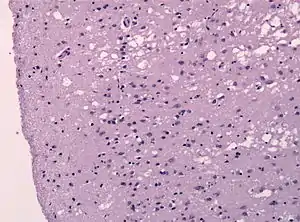

![]() Гистологический препарат — ткань лобной доли головного мозга больного болезнью Крейтцфельдта — Якоба | |

Прионы вызывают нейродегенеративные заболевания, так как образуют внеклеточные скопления в центральной нервной системе и формируют амилоидные бляшки, которые разрушают нормальную структуру ткани. Разрушение характеризуется образованием «дыр» (полостей) в ткани, и ткань принимает губчатую структуру из-за формирования вакуолей в нейронах[65]. Другие наблюдаемые при этом гистологические изменения — астроглиоз (увеличение численности астроцитов из-за разрушения близлежащих нейронов) и отсутствие воспалительных реакций[66]. Хотя инкубационный период прионных заболеваний, как правило, очень долог, после появления симптомов болезнь прогрессирует быстро, приводя к разрушению мозга и смерти[67]. Проявляющимися при этом нейродегенеративными симптомами могут быть конвульсии, деменция, атаксия (расстройство координации движений), поведенческие и личностные изменения.